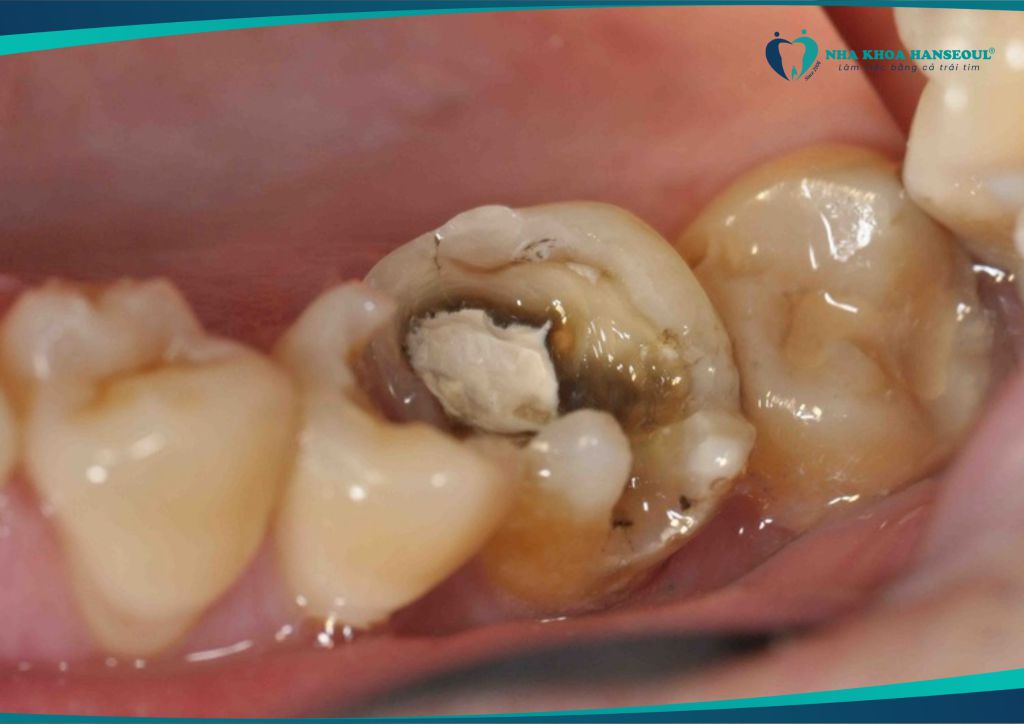

2.1 Gây sâu răng số 7 – răng hàm quan trọng

Răng số 8 mọc lệch thường đâm vào răng số 7, tạo thành khe hẹp khó vệ sinh. → Thức ăn mắc lại lâu ngày dẫn đến sâu răng số 7, viêm tủy, thậm chí mất răng vĩnh viễn.